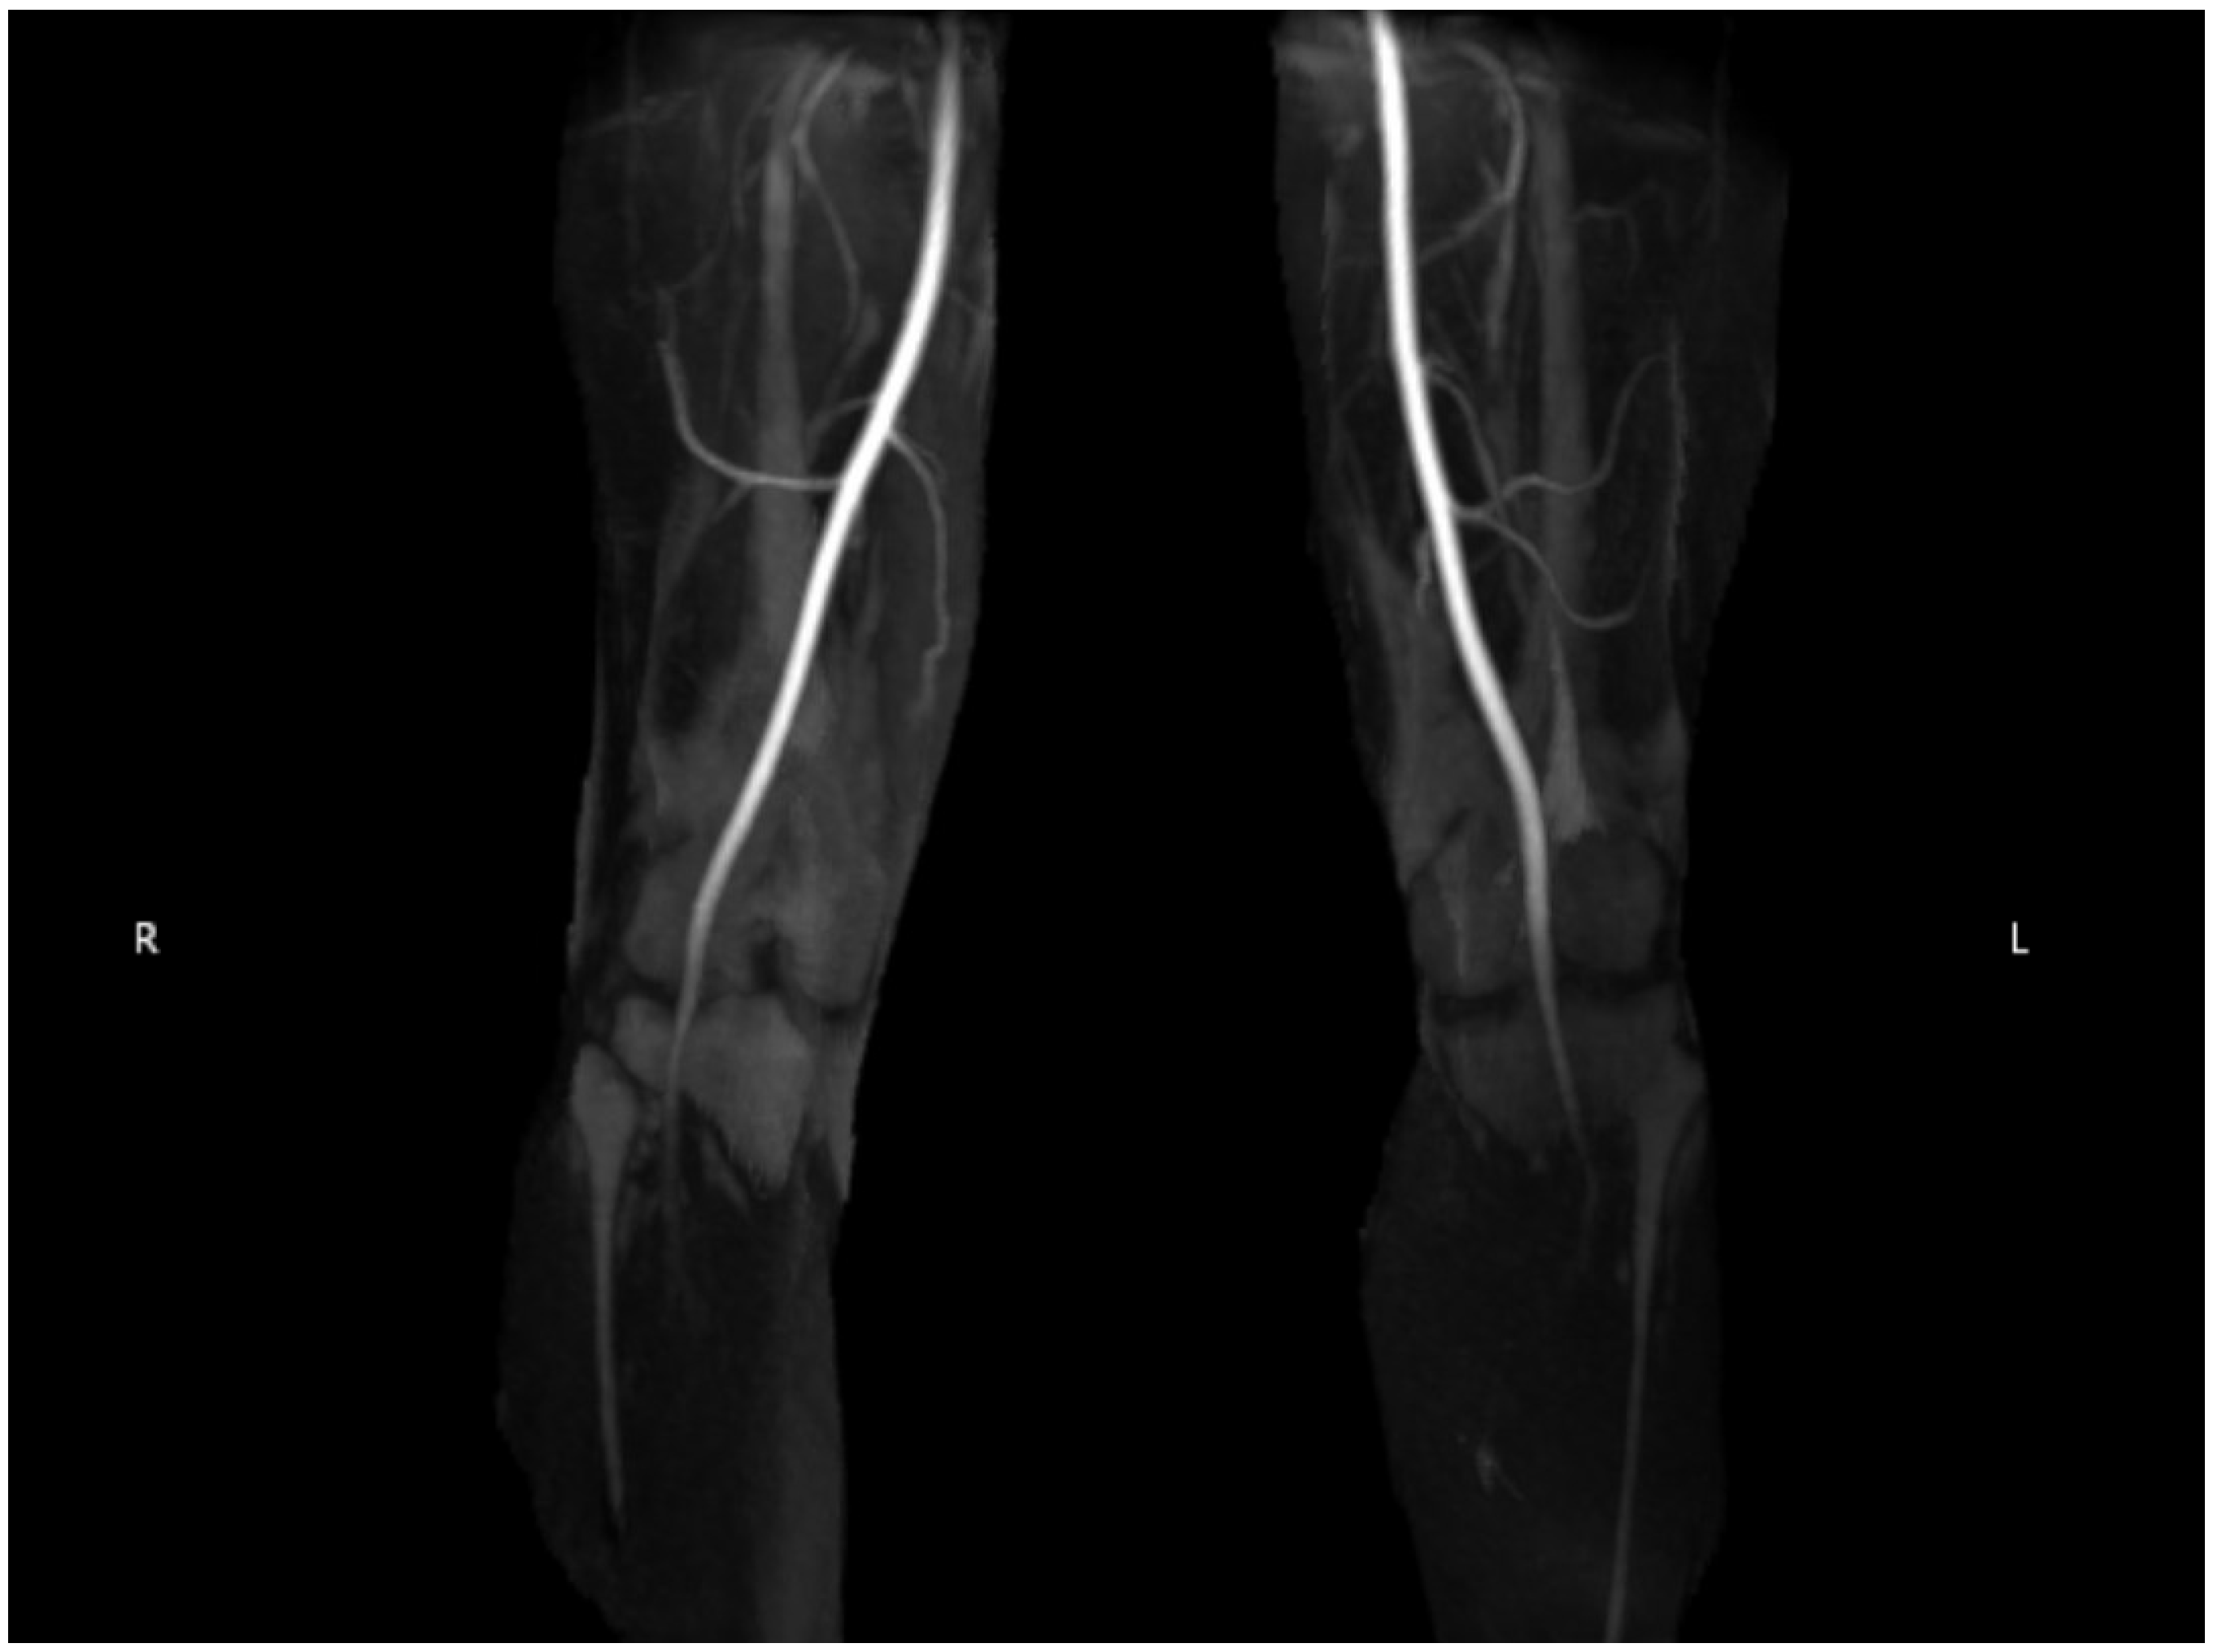

2.2. Diagnostic Testing

3.5. Modalities of Imaging